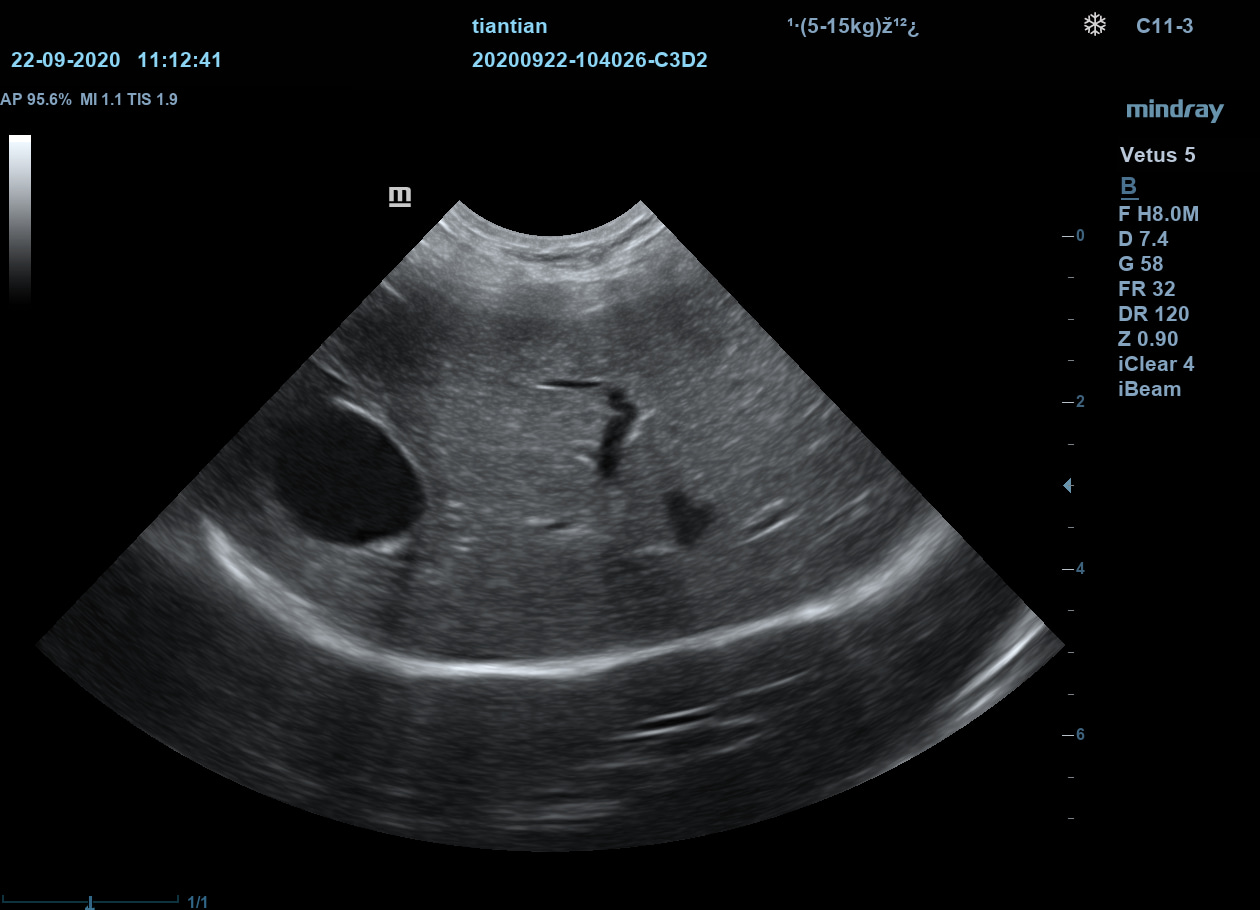

Ветеринарный ультразвуковой аппарат Mindray Vetus 5 использует новейшие технологии и ПО и позволяет проводить скрининг внутренних органов животных, получая чёткие и достоверные данные об их структуре, размерах и расположении.

Позволяет получать УЗИ-изображения с учётом анатомических особенностей животных.

Подразделяет животных по размеру и весу для максимально точной диагностики.

iClear

Визуализация с подавлением зернистости. Улучшение качества изображения за счет автоматического распознавания структуры тканей.